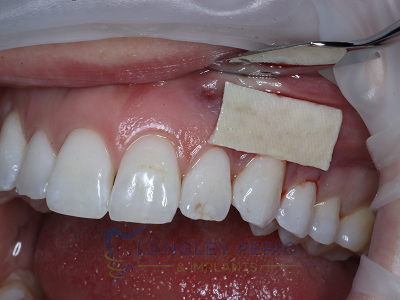

Case 1

Connective tissue grafting was performed to correct gingival clefting caused by over-aggressive toothbrushing